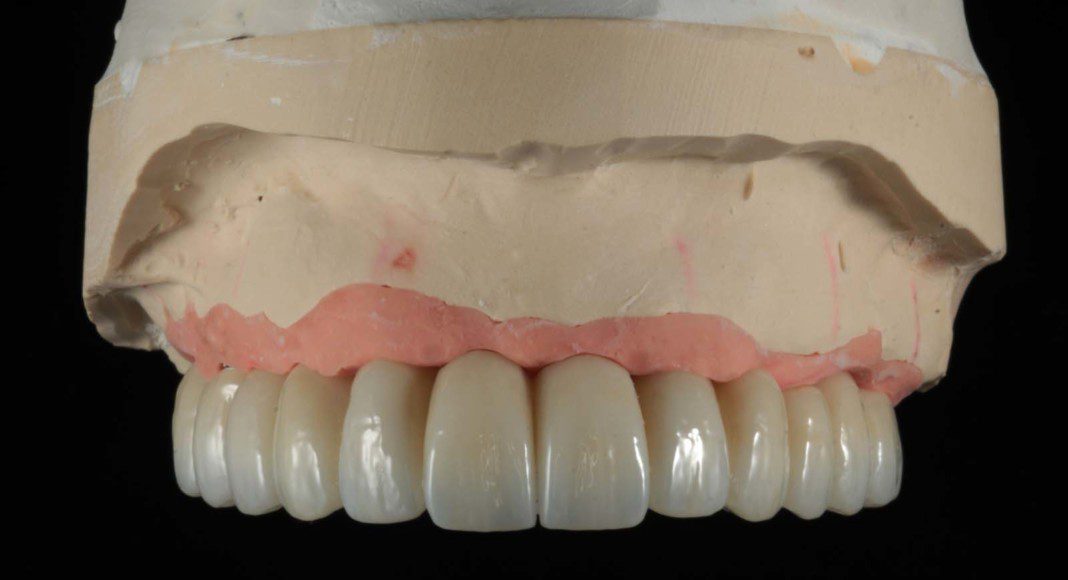

Prototype-wax-up-try-in. Used to determine length, width, overall smile, and bite (full face, smile).